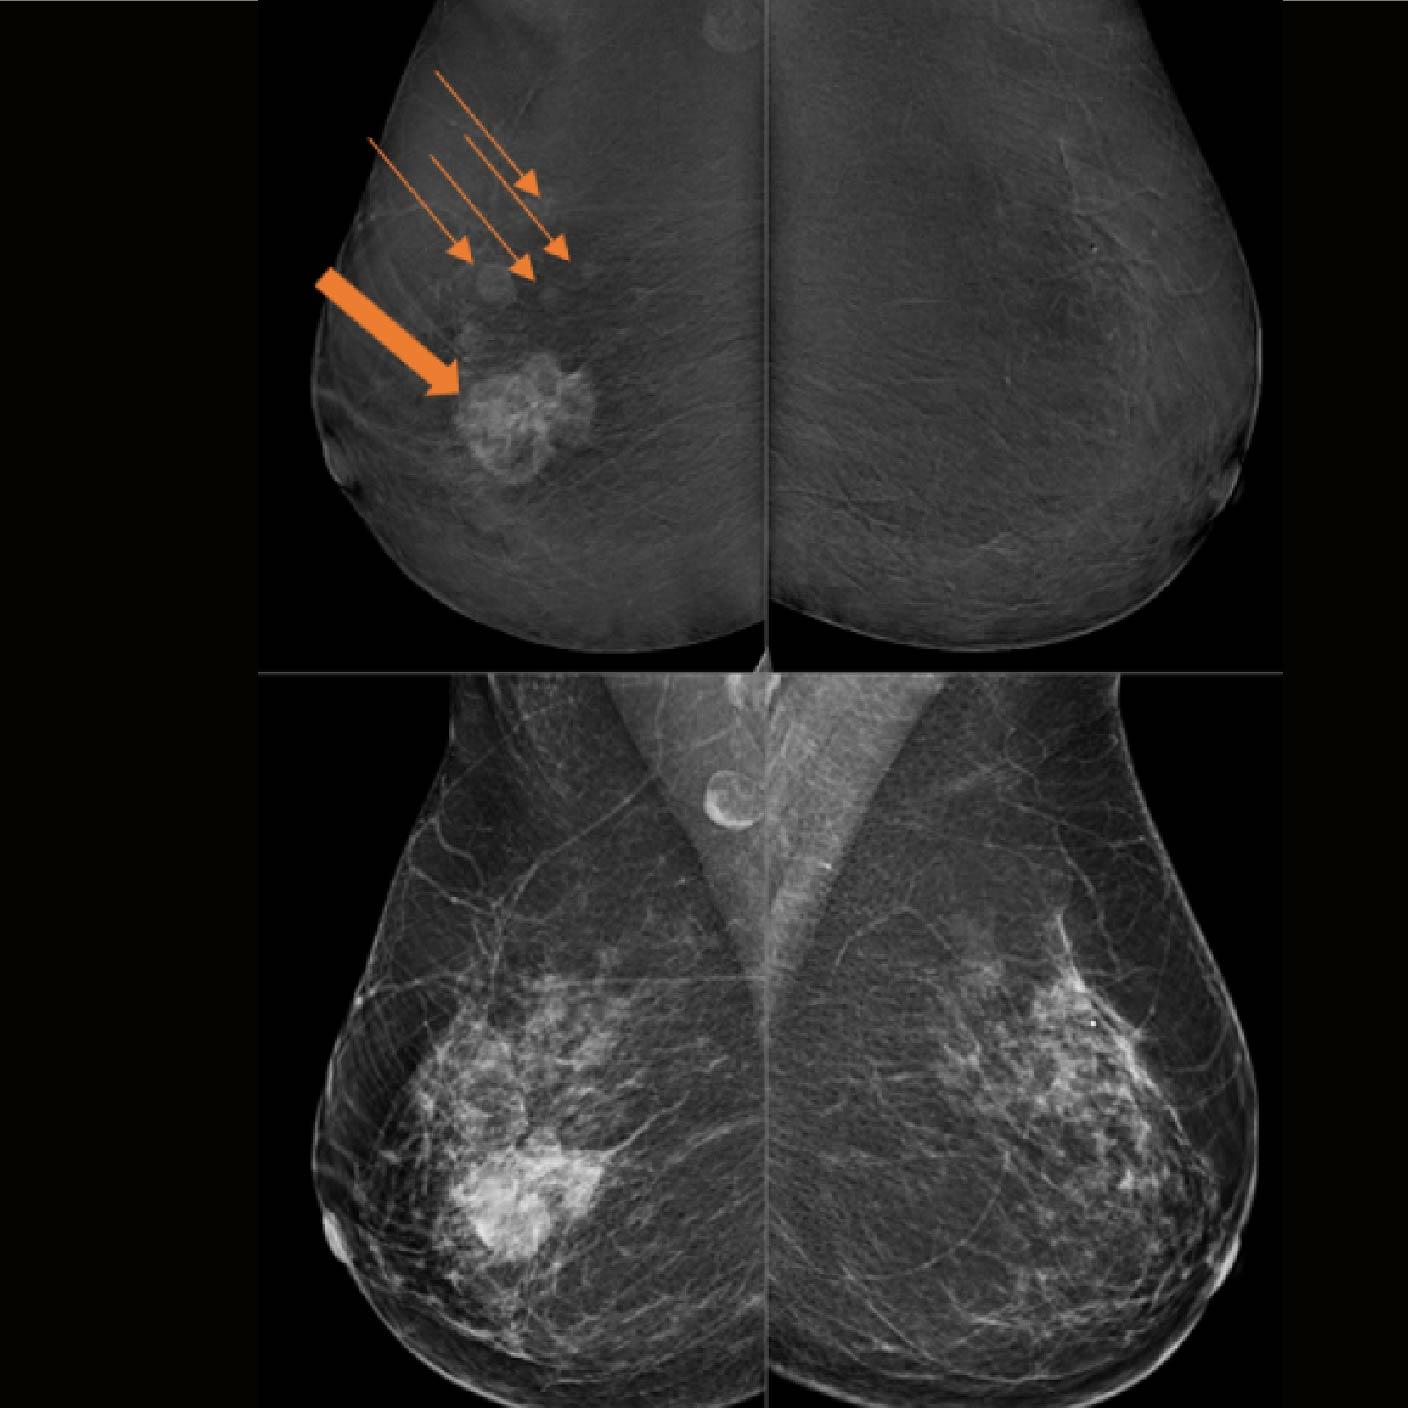

Valoración con TiCEM

- Confirmación de una masa asimétrica en el cuadrante externo de la mama derecha.

- Detección de otros 4 focos (flechas) que muestran realces variables en un diámetro total de aprox. 70 mm

- Se realizó una Biopsia trucut guiada por ecografía en la masa multifocal del seno derecho.

- Se asigna un Bi-RADS 5 en la mama derecha y un Bi-RADS 1 en

la mama izquierda

La patología reportada fue un carcinoma ductal in situ grado 2 (9 horas) y un carcinoma ductal in situ grado 3 (10 Horas) en la mama derecha.